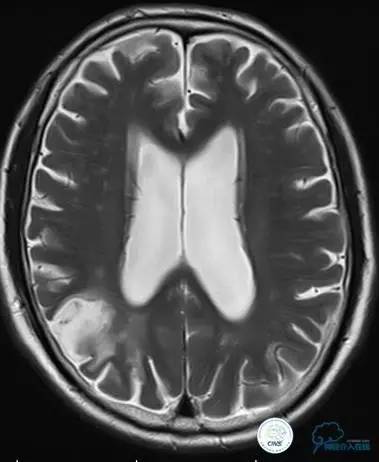

患者:58岁男性,反复头晕、肢体无力3月,当地造影见多发颅内动脉狭窄、闭塞,转来我院。

▼首先行颈动脉CTO开通术,手术顺利,Wallstent支架。

▼1周后行右侧椎动脉V4段CTO开通术。

▼微导丝穿过狭窄段,微导管造影,小球囊预扩张,2mm。

▼根据血管情况选择较大球囊再次预扩张。

▼置入2枚Wingspan支架,手术成功。

▼术后即刻CT,梗死灶内再灌注出血。

患者无症状,中性治疗。4月21日电话随访,一般情况好,当地CT示出血吸收期。